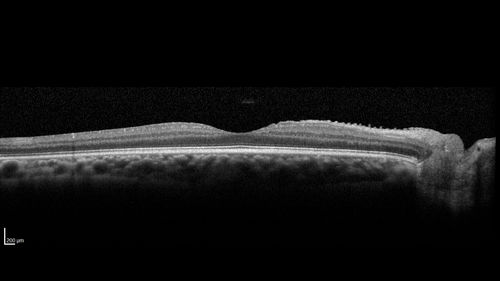

Eales Disease and fresh vitreous hemorrhage - 20 year old man

20 year old mane with fresh vitreous hemorrhage in the right eye.  At age 15 he had a PPV and laser in the left eye and laser in the right eye.  The vision is OD 20/80 PH 20/25, OS 20/25.  The left eye has a mild cataract.  He had prior testing for coagulopathies which was negative.  Testing done for syphillis and TB was negative.  Additional laser was done to prevent further bleeding in the right eye.